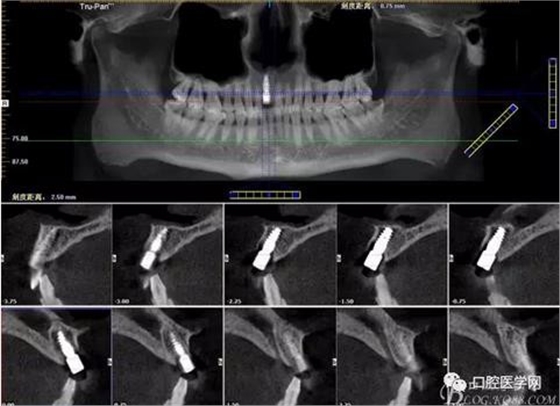

圖3 術(shù)后CT